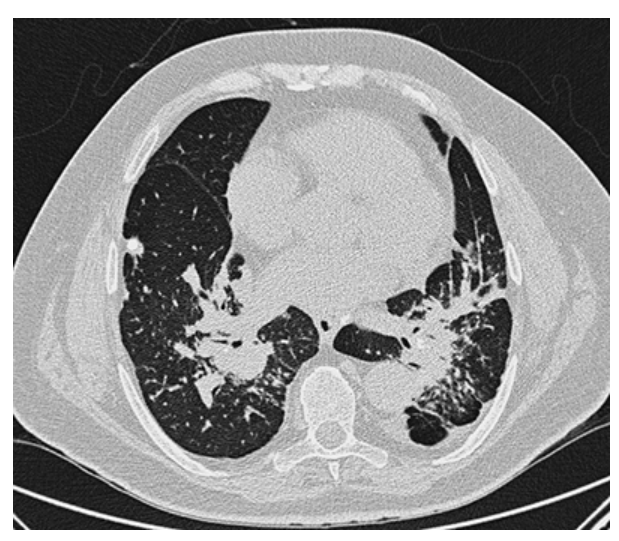

Hodgkin Disease. Contrast-enhanced CT shows a very large anterior mediastinal mass displacing the aortic arch posteriorly and compressing the trachea. This mediastinal mass in this young patient is consistent with lymphoma or Hodgkin disease.